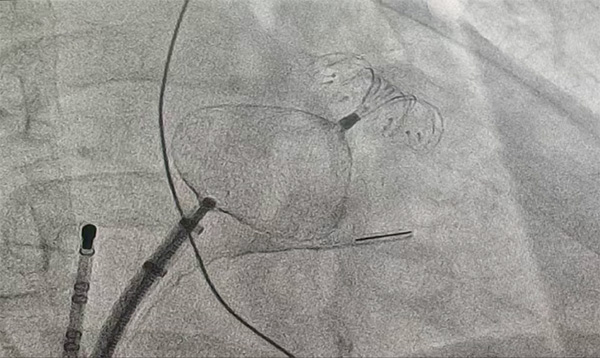

造影:通过造影可见心耳为菜花型,心耳存在两个分叶,且心耳内肌小梁很发达,预定进行嵴外封堵。

测量:通过测量心耳的锚定区为24-25mm,封堵区为29-31mm,综合选择2834LAmbre进行封堵尝试。

植入:采用渐进式的方式植入封堵器,过程中遇到了一定的困难,固定盘下缘进入心耳后整个盘无法完全展开,在保证固定盘展开的情况下无法将其送入心耳;考虑原因为伞盘过大,决定更换封堵器。

再次测量:更换封堵方案,再次测量心耳的锚定区为20-23mm,封堵区为29mm,综合选择2436LAmbre进行封堵。

植入过程:通过渐进式植入固定盘,在右肩位及肝位确定固定盘抵达预定位置且完全展开。